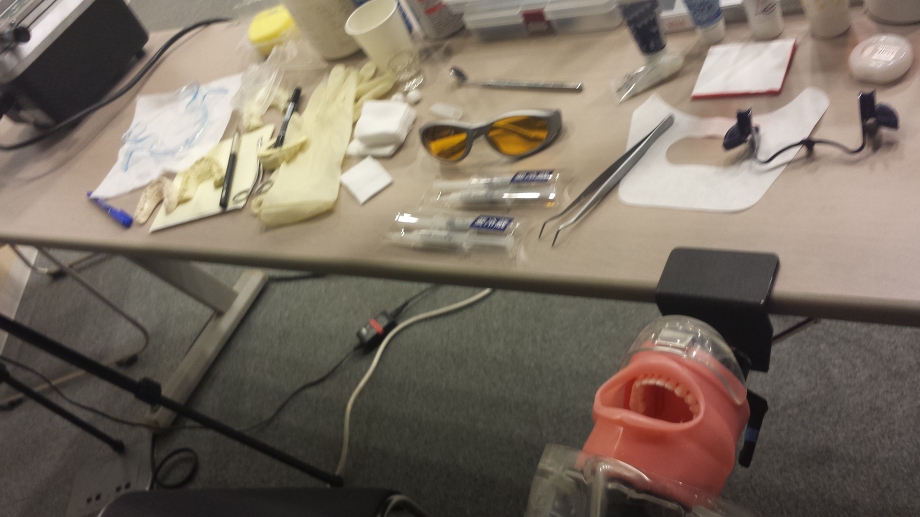

![]() 歯を白く漂白するホワイトニング

歯を白く漂白するホワイトニング